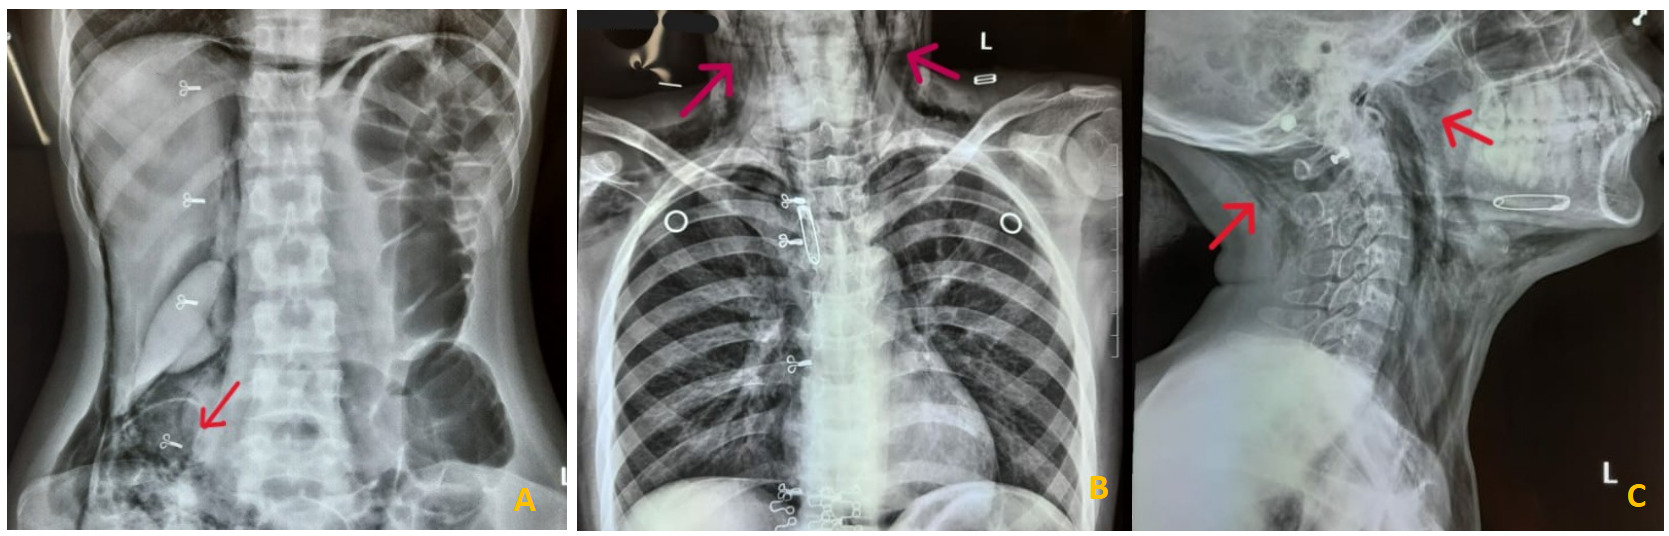

Due to her complaint of mild abdominal discomfort, an abdominal X-ray was ordered. Shortly afterward, she developed shortness of breath and progressive subcutaneous emphysema in the neckThere were no signs of stridor or cyanosis, and her vital signs were stable except for tachycardia. On abdominal examination, the abdomen was soft with normal bowel sounds. Laboratory tests revealed an elevated CRP of 25 mg/L (normal <1 mg/L), a raised total white blood cell count of 13,000/µL (normal 4,000–11,000/µL), low albumin, and hemoglobin at 10 g/dL (normal 11–15 g/dL). All other laboratory parameters were within normal limits, and HIV testing was negative. The abdominal plain radiograph in the anteroposterior (AP) view showed air lucencies centered in the right iliac fossa extending along the right psoas muscle, consistent with pneumo-retroperitoneum(Figure 1A). Clear demarcation of the right renal margin was also noted. Air lucencies further extended along the right suprarenal region and superiorly till the diaphragmatic undersurface in the midline. No air was noted under the bilateral hemidiaphragms, suggestive of the absence of significant intraperitoneal free air. Air was seen extending along the right lateral pre-peritoneal fat plane cranially as well. A plain radiograph of the chest PA view showed extensive soft tissue emphysema along the bilateral sternocleidomastoid muscles as evidenced by air lucencies within (Figure 1B). The soft tissue emphysema was noted to dissect along the fascial planes to involve other neck muscles as well. Pneumomediastinum was also present. A plain radiograph of the neck lateral view revealed the soft tissue emphysema involving the anterior and posterior neck muscles extending cranially to the skull base (Figure 1C).